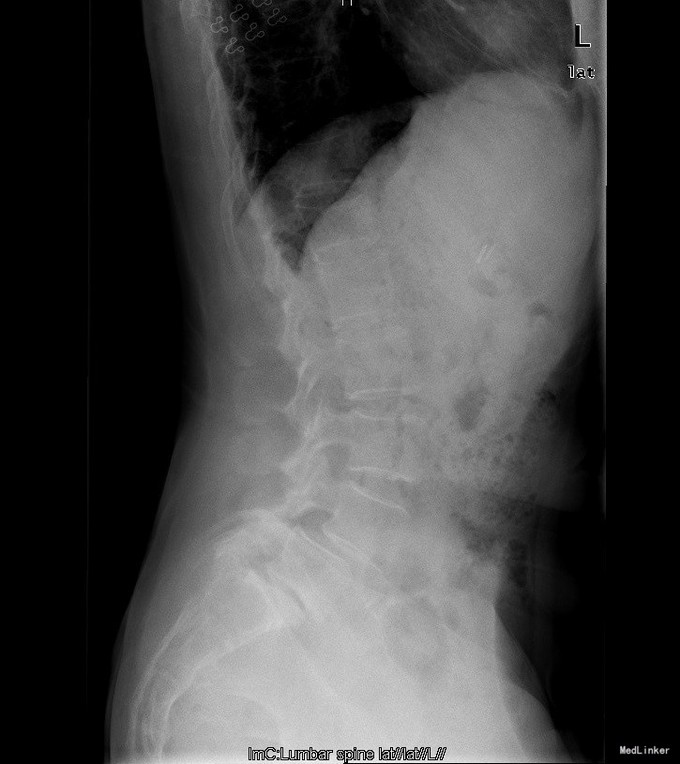

主诉:反复腰部疼痛20+年,加重伴双下肢胀痛麻木 现病史:患者于20+年前,因车祸行腰椎检查发现腰4椎体I°滑脱,并感腰部阵发性隐痛不适,一直未行特殊处理、4月前患者感腰部疼痛有所加重,并感双下肢阵发性胀痛麻木,久坐或弯腰后症状加重,以左下肢为甚,症状明显时难以直立行走,不伴畏寒发热、潮热盗汗等不适。10+天前患者在院外行理疗(具体不详),上述症状略有好转。在院外行腰椎x光摄片诊断为"腰4椎体II°滑脱,腰5椎体I°滑脱",故来我院就诊,门诊以"腰椎滑脱"收入住院

查体:脊柱外观无侧弯后突畸形,双下肢无肌肉萎缩。腰4-5、腰5骶1棘上棘旁轻压痛,伴左侧下肢放射;会阴部感觉未见异常,双侧小腿前外侧及足背足底感觉减退。腰椎前屈后伸及侧屈活动度正常;双下肢髂腰肌肌力4级,左侧直腿抬高试验阳性,加强试验阳性,左侧膝腱反射减弱,双侧病理征未引出。 辅助检查:院外腰椎正侧位片:腰4椎体II°滑脱,腰5椎体I°滑脱。

诊断:腰4椎II°滑脱症,腰5椎I°滑脱症 治疗:经后路腰4、5椎切开复位、椎管减压、Capstone椎间及后外侧人工骨+自体骨植骨融合、Legacy内固定术